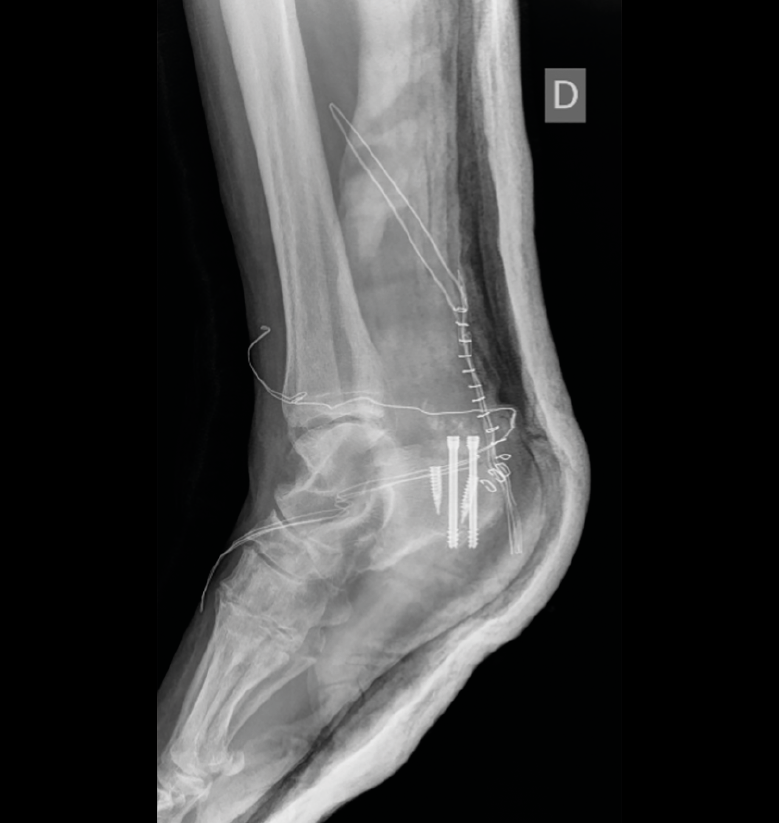

El tratamiento aplicado, 3 días después de la lesión, consistió en la reducción abierta y osteosíntesis con tornillos canulados. Se asoció una reinserción aquílea con 2 arpones tras observar también una desinserción parcial del tendón respecto al fragmento de tuberosidad (Figura 3). Finalmente, se colocó una botina de yeso en equino.

Figura 3. Resultado radiológico final. Se aprecia la osteosíntesis con tornillos canulados y arpones para la reinserción tendinosa.